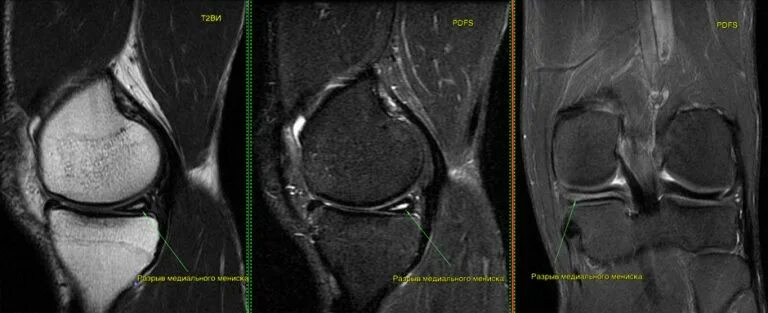

Дегенеративное повреждение внутреннего мениска 2 степени